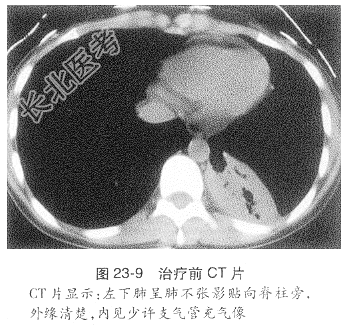

- [材料题] 患者,女性,21岁,主因“刺激性干咳2年,加重1个月”入我院。患者于2年前无明显诱因出现刺激性咳嗽,以干咳为主,偶有黄痰,诊断为“上呼吸道感染”,经抗感染治疗后咳痰好转,但仍有咳嗽。2年来反复多次出现咳嗽、咳痰加重,均经抗感染治疗后好转。入院前1个月前受凉后咳嗽加重,伴咳白痰,伴发热,体温37.5~38℃,以午后为著,经抗感染治疗后无好转,为进一步诊断治疗收入我院。入院后查胸部CT示纵隔及心脏轻度左移,右肺上叶尖后段及左上肺可见多发斑片、结节影,可见“树芽征”改变,左下肺呈肺不张影贴向脊柱旁,外缘清楚,内见少许支气管气像,左主气管及左侧各叶支气管狭窄。纵隔未见肿大的淋巴结。心脏、大血管未见异常。左侧胸腔少量积液。气管镜示气管下端左侧壁、左总、右上可见肉芽肿,表面坏死;左总远端肉芽肿表面坏死,坏死占据管腔1/2,支气管镜不能进入检查(图23-8~图23-11)。其他辅助检查:血抗结核抗体(Lam-Ab)阳性,血沉:94mm/h,痰抗酸杆菌2+,结核分枝杆菌快速培养阳性。